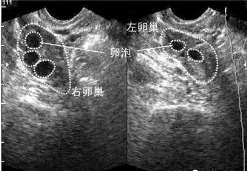

746 好孕百科武汉供卵做三代试管 卵泡数量与试管婴儿的成功率有很大的关系,很多女性因为卵巢功能差,卵泡少不能自然过怀孕从而选 […]